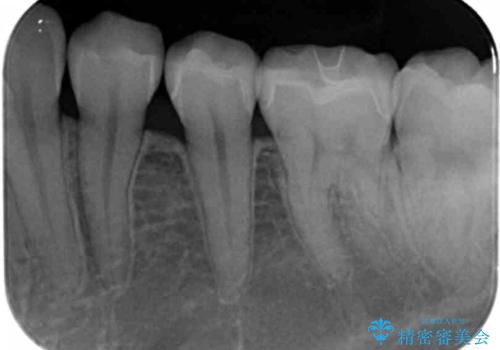

歯と歯の間の虫歯 セラミックインレーでの治療

- 矯正前の虫歯治療です。

歯と歯の間に虫歯があったため適合の良いセラミックインレーで修復処置をしていきました。

- 左下567 セラミックインレー 77,000円×3本費用は治療当時の料金となります

歯と歯の間は虫歯の好発部位となっています。

適合の良いインレーでの修復により再発のリスクを下げることができます。